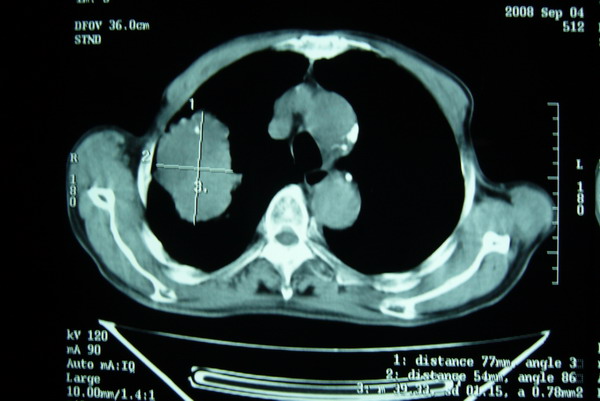

标题: CT15579:男 86岁 咳嗽 咳少量白痰 发热2天 吸烟史60年 [打印本页]

标题: CT15579:男 86岁 咳嗽 咳少量白痰 发热2天 吸烟史60年

分叶及少量边缘性钙化,老年人,周围性肺癌首先考虑。

右肺上叶巨大软组织肿块,轮廓不规则,纵隔内有肿大淋巴结,首先考虑肺癌。

右上肺一不规则团块,边缘有分叶和毛刺,纵隔有淋巴结肿大。右肺周围性肺癌首先考虑。